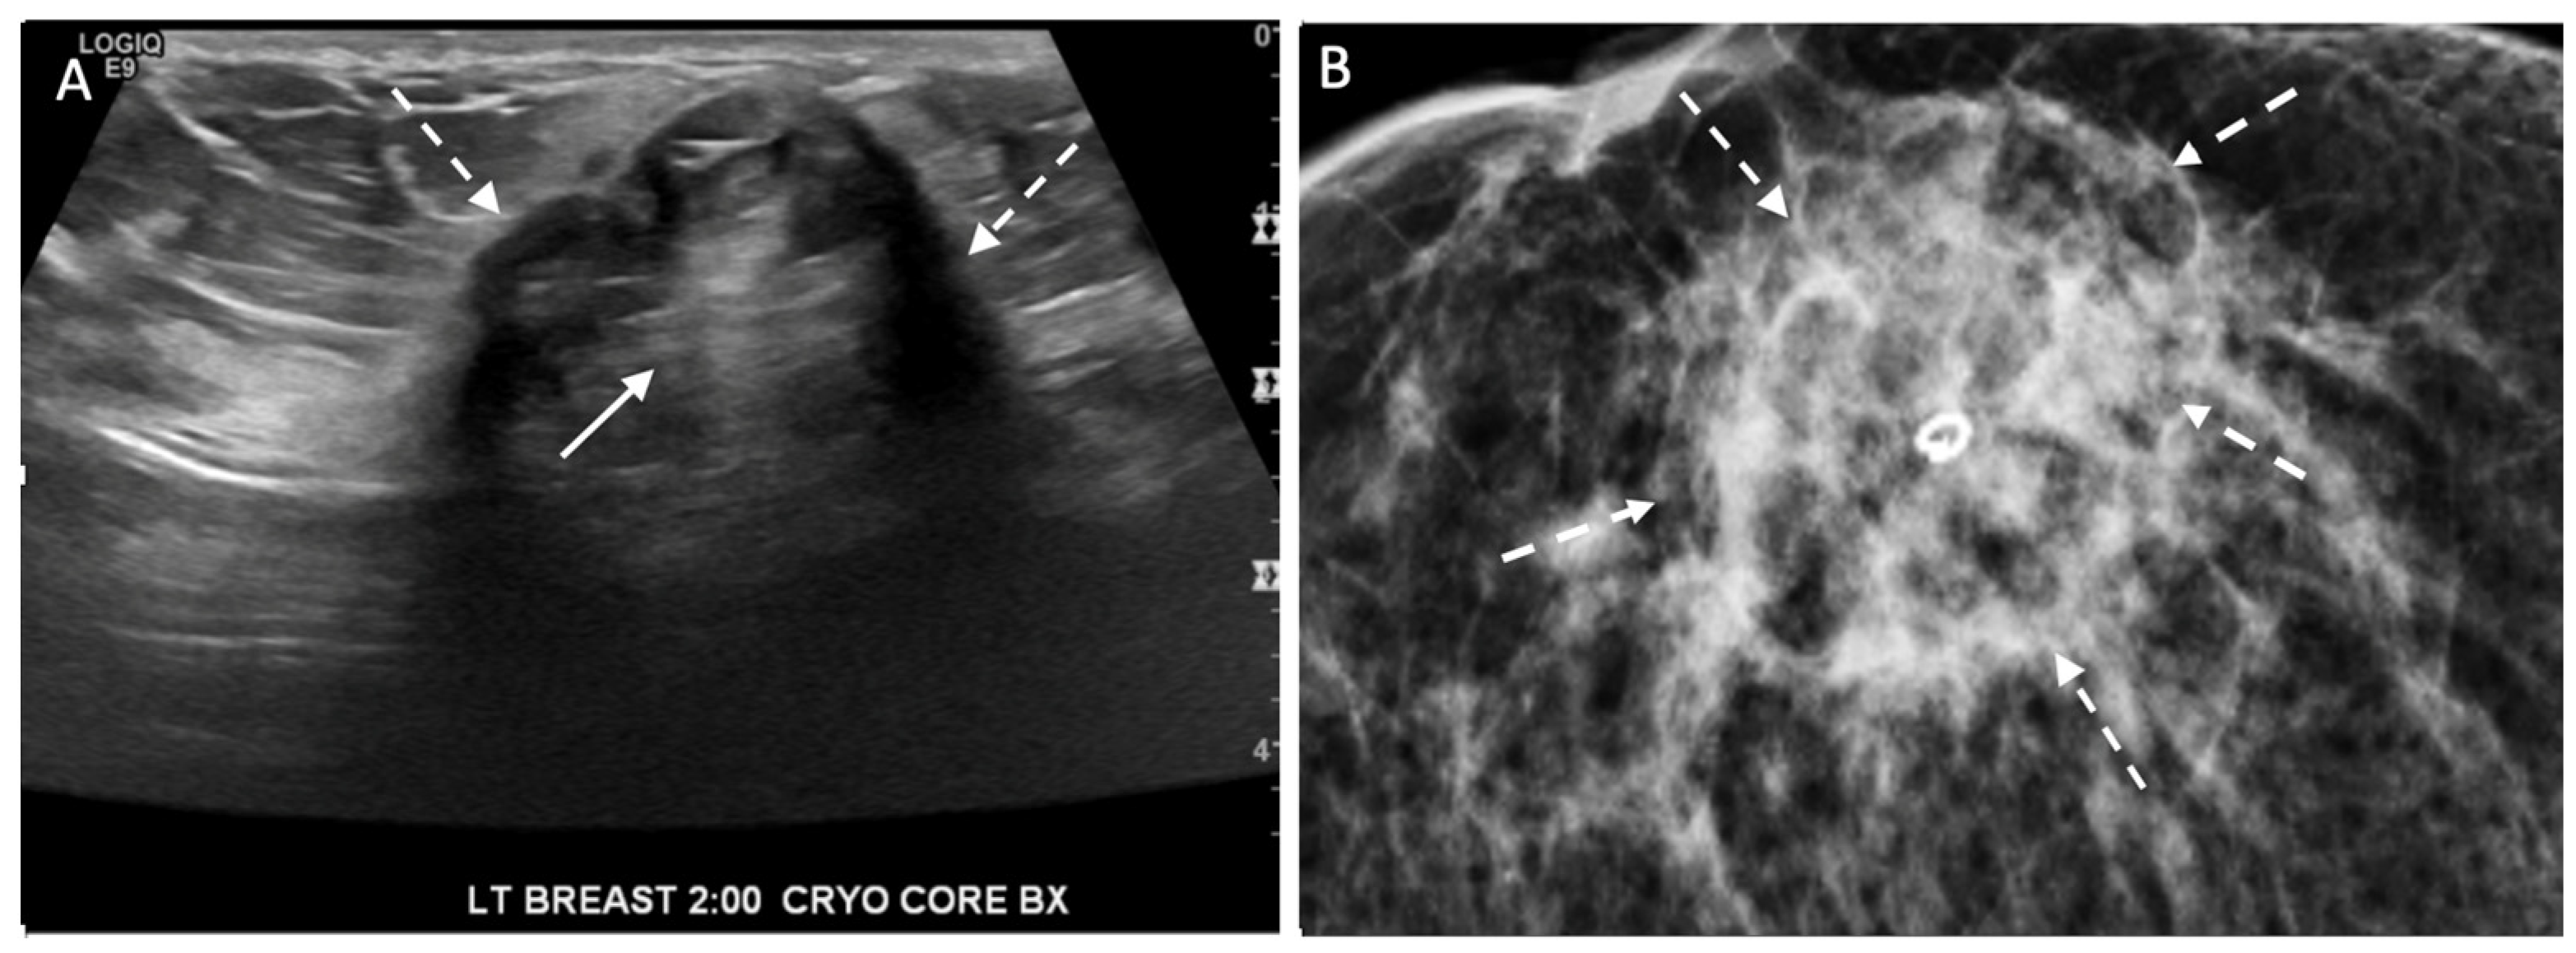

Ultrasound of the breast. Office-based cryoablation is optimized for treatment of ultrasound-visible breast cancers. Consequently, breast ultrasound should be performed of all suspicious imaging abnormalities to assess eligibility for ultrasound-guided cryoablation. Ultrasound permits assessment of the cancer’s proximity to the overlying skin and underlying chest wall and also enables detection of changes in adjacent tissue architecture (e.g., edema, tissue distortion, extension of tumor into adjacent ducts) and could indicate the presence of more extensive disease that would need to be incorporated into the treatment plan (Figure 2). Proximity (<5 mm) of a cancer to the skin is generally regarded as a contraindication to cryoablation, but a safe skin distance can sometimes be created using hydrodissection or injection of saline between the tumor and overlying dermis.

Figure 2.

(A) shows dark, dominant, irregular mass encircled by hash marks with intraductal tumor extensions (dark bands bracketed by paired arrows) extending from left and right sides of dominant mass. (B) shows dark, irregular dominant mass (arrow) surrounded by peri-tumoral edema outlined by hash marks.

Ultrasound of the axilla. Axillary ultrasound permits the detection of abnormal appearing lymph nodes that might not be detected on physical examination, mammography, or breast MRI. Axillary ultrasound is the most sensitive imaging study for the detection of subtle changes in the shape or thickness of a lymph node cortex that might indicate the presence of lymph node metastasis (Figure 3). Detection of suspicious lymph nodes determines clinical cancer stage and requires a specific plan to manage the possibility of lymph node metastasis.

Figure 3.

Hash marks outline abnormal appearing axillary lymph node measuring 1.5 cm in maximal diameter. Paired “+” marks indicate the span of a 0.4 cm area of focal cortical thickening that is suspicious for a metastatic deposit within the lymph node.